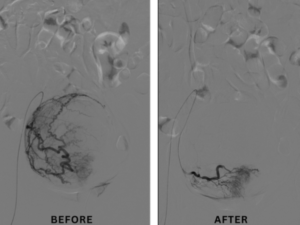

Medical advancements have made it possible to treat fibroids using image-guided techniques. These procedures are designed to target fibroids precisely without damaging surrounding tissues. One of the most commonly used methods is uterine fibroid embolization (UFE), where the blood supply to fibroids is blocked, causing them to shrink gradually.

This approach is minimally invasive and performed by trained specialists using advanced imaging tools. Many patients now prefer Non-Surgical Fibroid Treatment Bengaluru for its precision and effectiveness.

Minimally invasive fibroid treatments are known for their long-term benefits. By addressing the root cause, these procedures provide lasting relief from symptoms. Many patients experience improved energy levels, reduced discomfort, and better overall health.